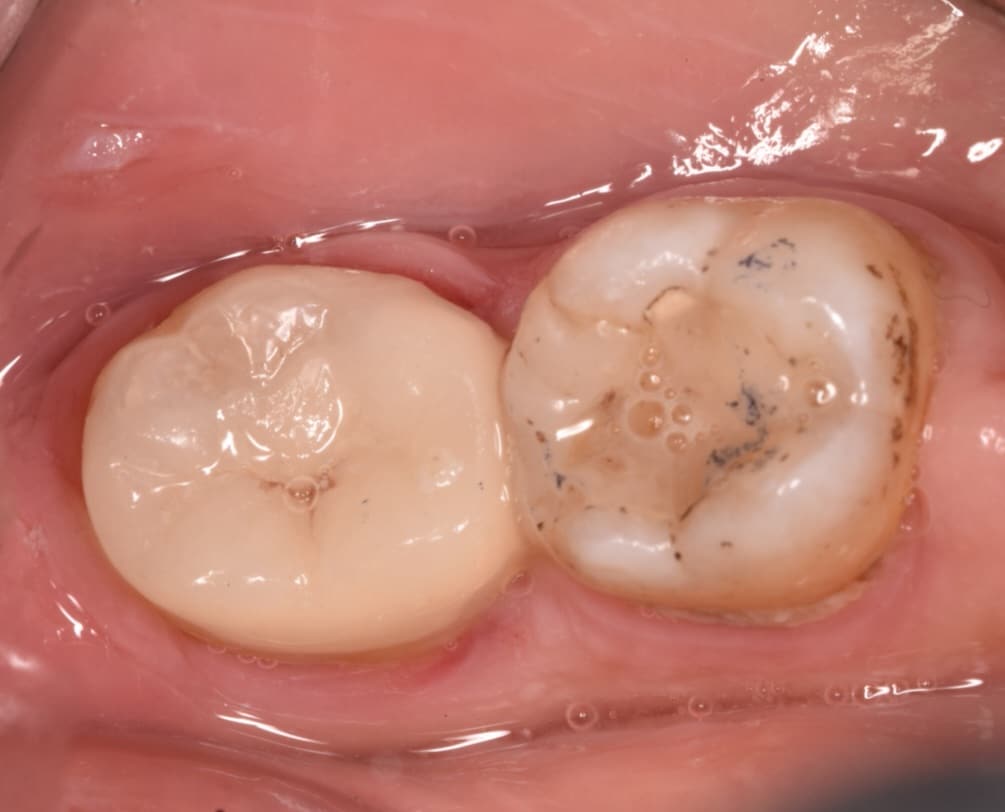

After removing the old filling and complete cavity design

IDS with gold standard cleafil SE bond